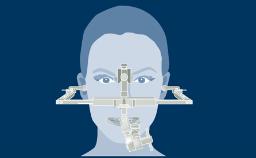

Structured Assessment and Treatment Planning

Extraoral Clinical Examinations

Learning Module